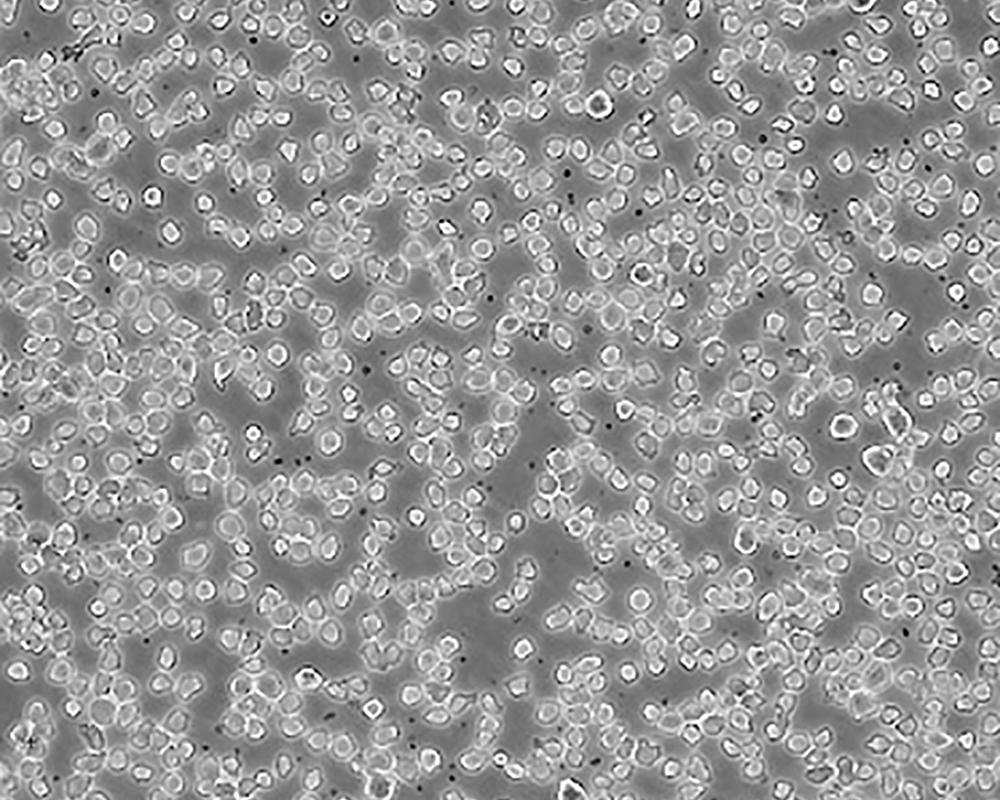

THP-1

產(chǎn)品名稱 THP-1

中文名稱 人單核細(xì)胞白血病

組織來(lái)源 急性單核細(xì)胞白血病;男性

細(xì)胞種屬 Homo sapiens, human

生長(zhǎng)特性 suspension

形態(tài)特征 monocyte

細(xì)胞描述 該細(xì)胞從一名1歲的患有急性單核細(xì)胞性白血病的男孩的外周血中分離建立。該細(xì)胞可以吞噬乳膠顆粒和激活的紅細(xì)胞,細(xì)胞膜和胞漿內(nèi)均沒(méi)有免疫球蛋白,表達(dá)C3R和FcR;可受佛波酯TPA誘導(dǎo)向單核系方向分化;可作為轉(zhuǎn)染宿主。